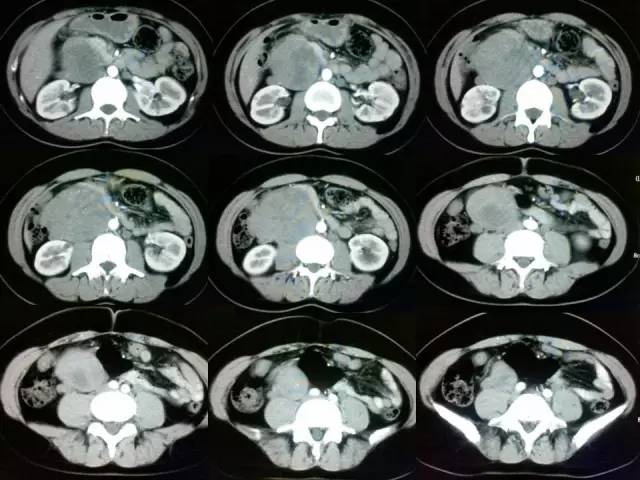

胰腺钩突下缘至右肾下极平面腹膜后内可见大小约8.3 cm×12.6的实行软组织密度肿块,增强边缘强化,其内可见无强化坏死区。肠系膜上动脉参与供血。十二指肠水平段受压向前上抬,肠系膜上动脉及上静脉受压左侧以为,内后侧紧贴腹主动脉,与腰大肌分界消失。